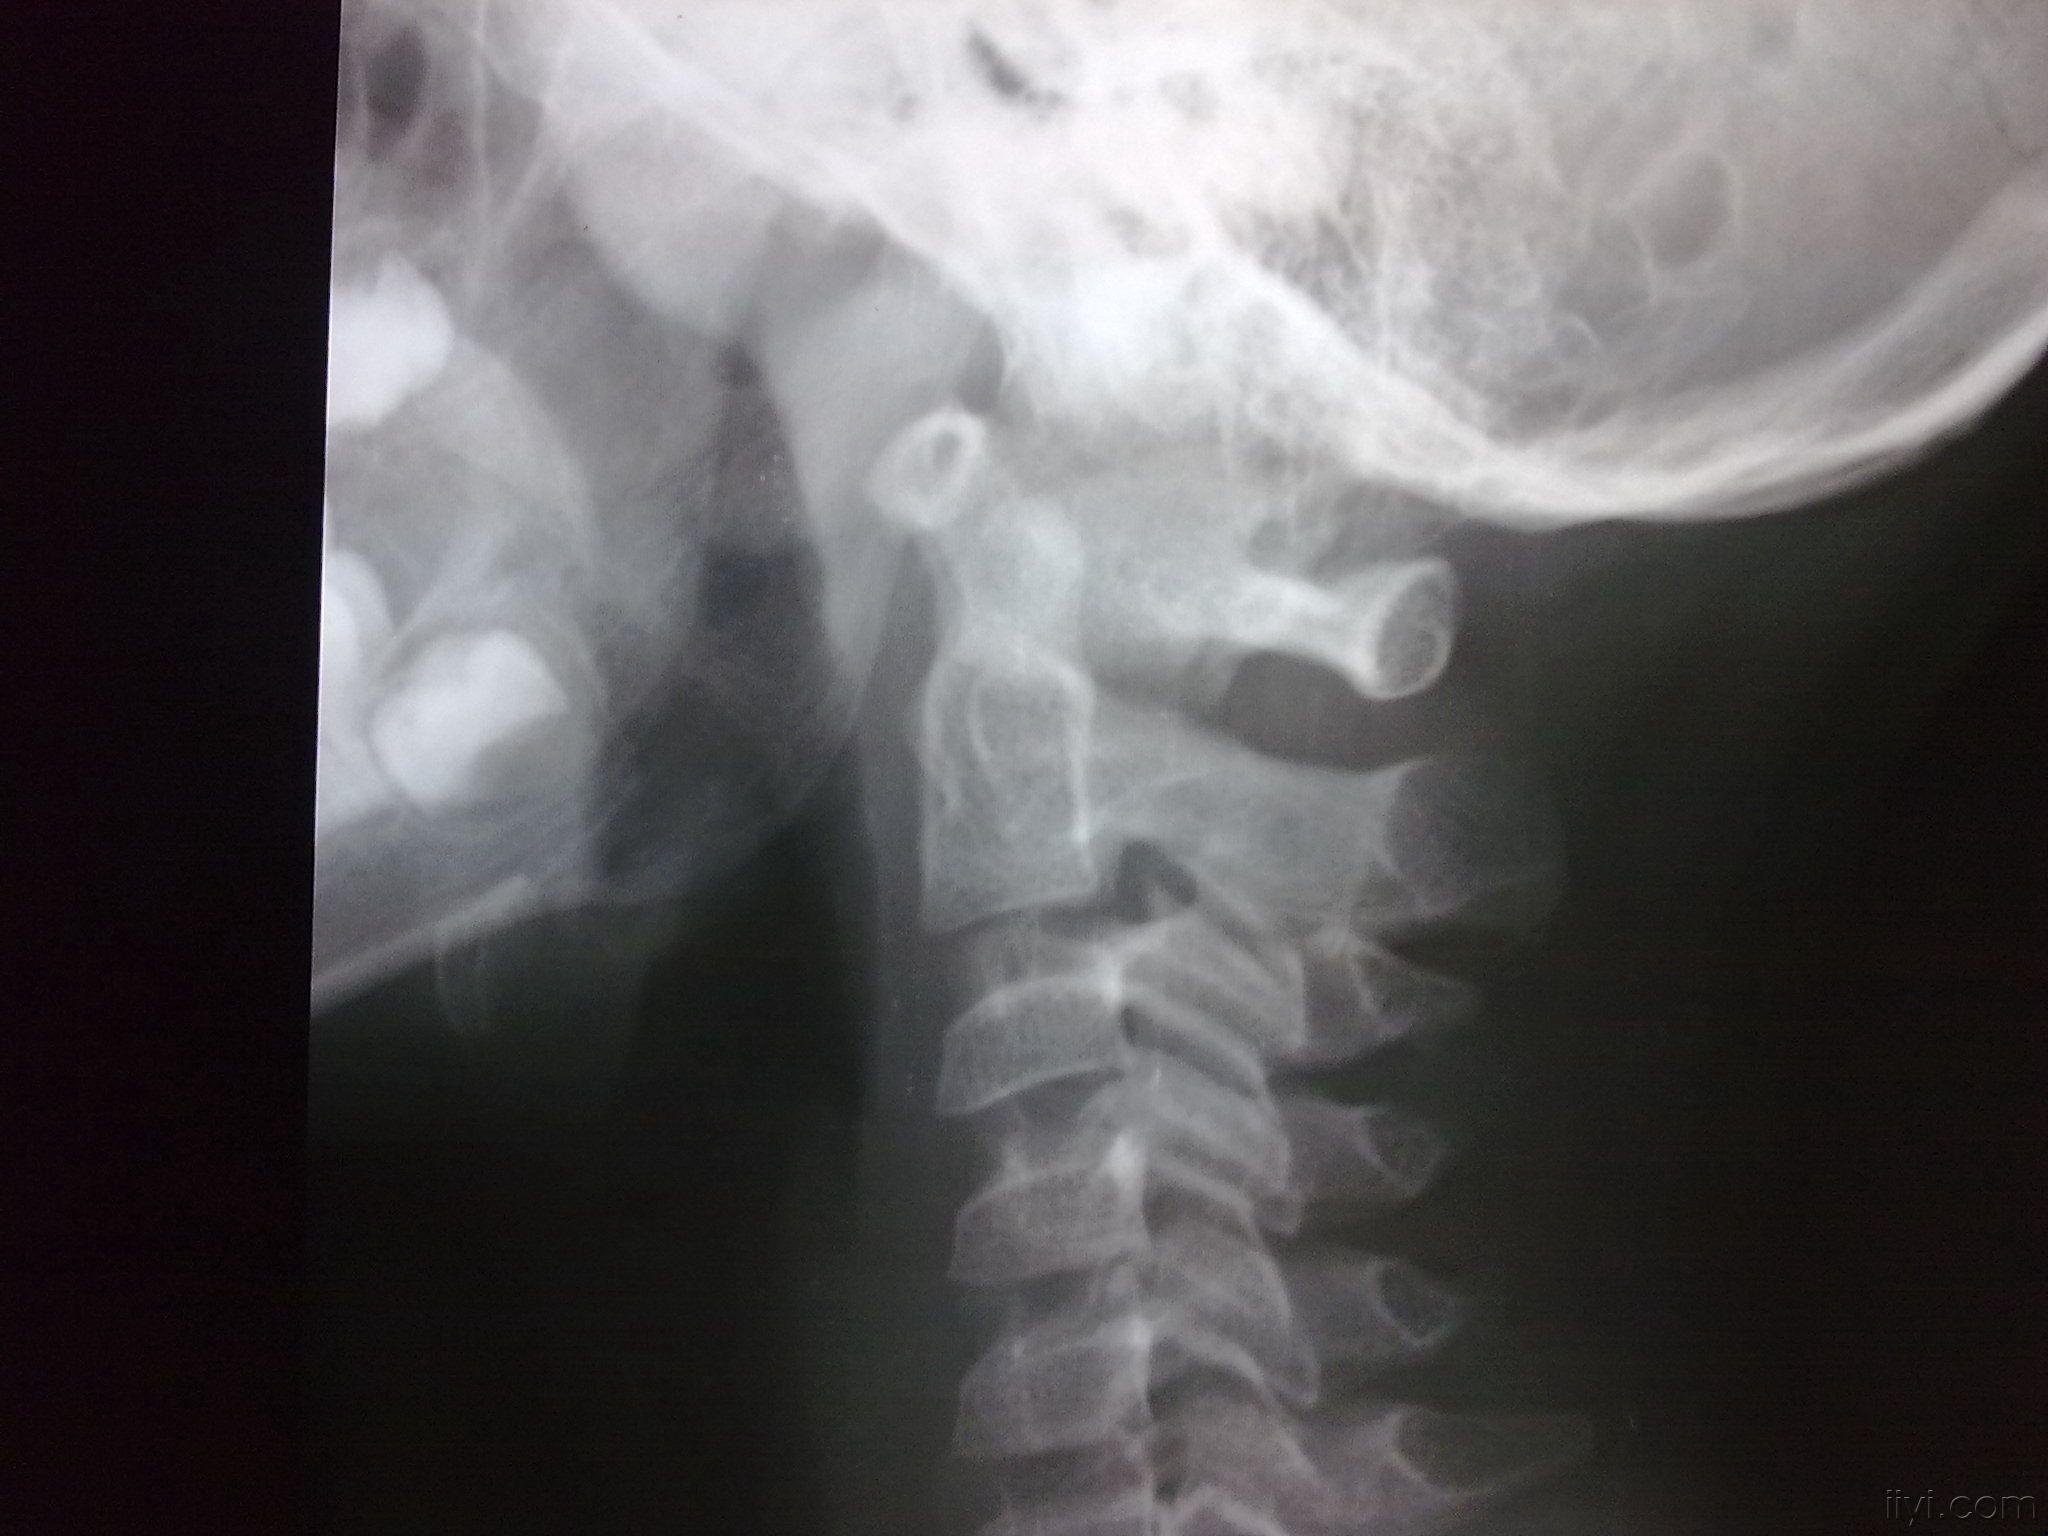

寰枢椎半脱位

寰椎前弓骨折并环枢椎侧脱位

new0263:寰枢外侧关节半脱位

病例一:患者女性,49岁,因颈部活动受限4月入院,诊断为寰枢椎脱位,颅底